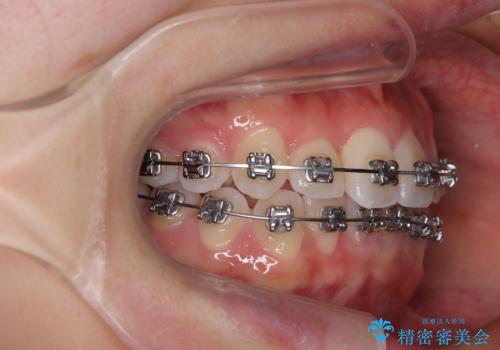

- メタルブラケット

装置の外見を気にしていましたが、短期間で治療を終えることができるだろうと伝えると、安価であるメタルブラケットを選択されました。

想定通り、1年強で綺麗に仕上げることができました。